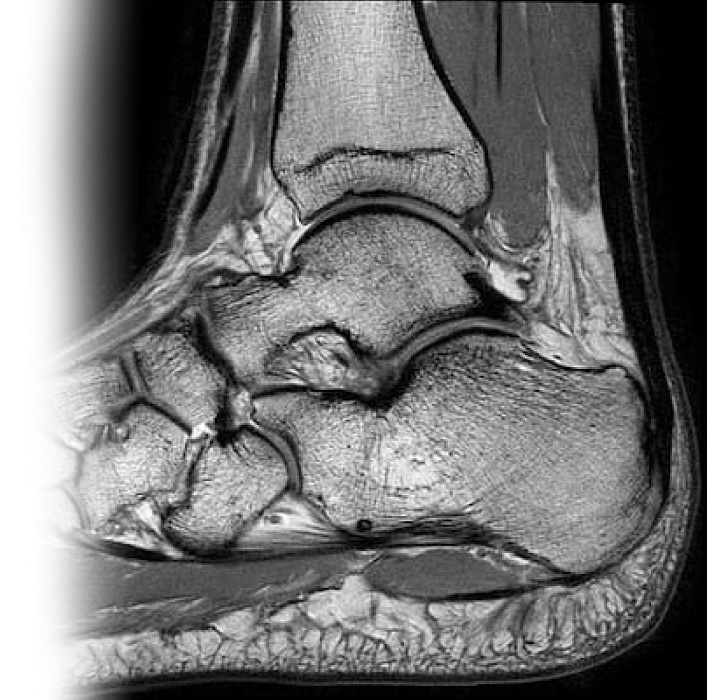

МРТ голеностопного сустава

Магнитно-резонансная томография голеностопного сустава – исследование, которое позволяет визуализировать костные структуры голеностопного сустава: дистальные отделы берцовых костей, пяточная кость, таранная кость, ладьевидная кость, кубовидная кость, клиновидные кости, связки, сухожилия, мышцы.